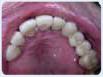

Reabilitare orala

• Se refera la refacerea fiecarui dinte din cavitatea orala a pacientului.

• Este nevoie de aceasta tehnica atunci cand dintii sunt tociti (abrazati),

sparti sau lipsesc.